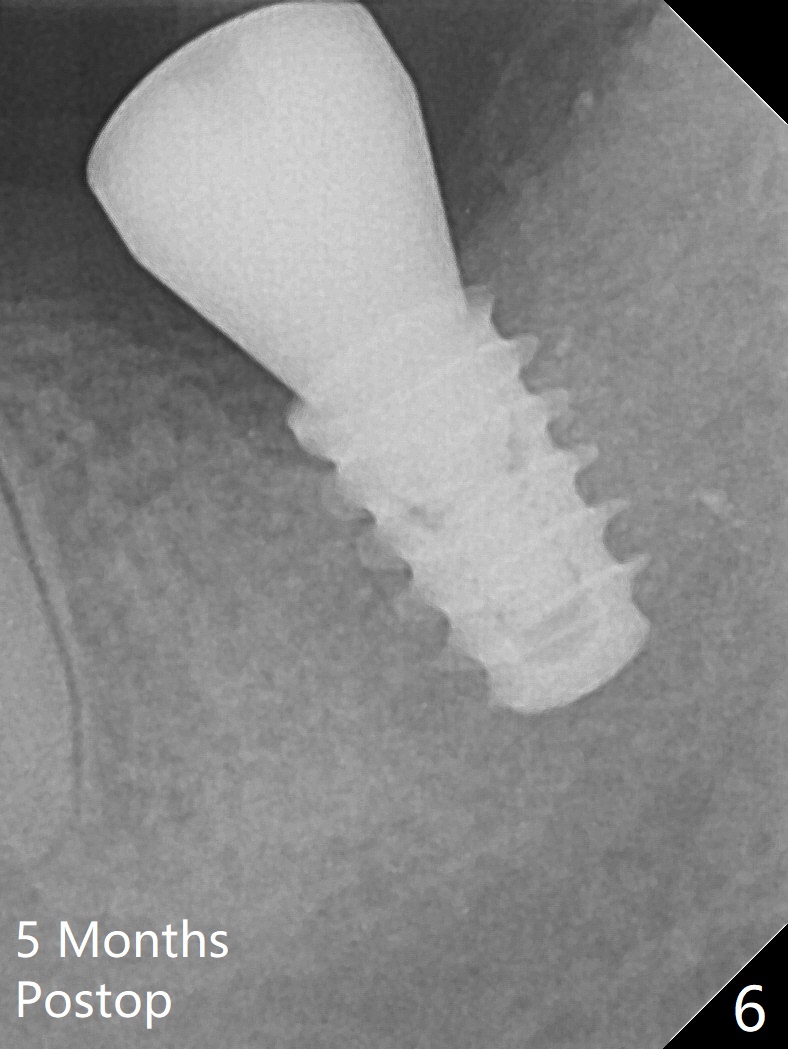

Six months post socket preservation at #18 (with moderate atrophy, Fig.1), a simplified surgical guide (Fig.2 with metal sleeve of 5 mm height and 2.93 mm diameter) determines initial osteotomy with 3.3 mm Magic Drill (MD), followed by 4.8 mm MD for 9 mm (gingival level) free hand. Since a 5x7 mm IBS implant is placed incompletely and in low stability (Fig.3 (in the graft bone)), a 4.3 mm MD is used for ~1 mm deeper. The implant is reseated to more satisfactory level (Fig.4: ~ 1 mm from the upper border of the Inferior Alveolar Canal (red dashed line)). The fearful patient is extremely pleased with quickness of the procedure as compared to that at #30 free hand. The wound heals normally 2 weeks postop. When she finishes the follow up appointment, she voluntarily talks to another patient who is hesitant about implant treatment. Impression is taken 5 months postop (Fig.5,6). There is no gap between the crown and abutment using abutcoping technique (Fig.7,8). The crown at #18 looks low probably related to long termed edentulism (Fig.9). The access hole is lingual (Fig.9), because the implant was placed lingual (Fig.10) due to use of a partial guide (Fig.11).